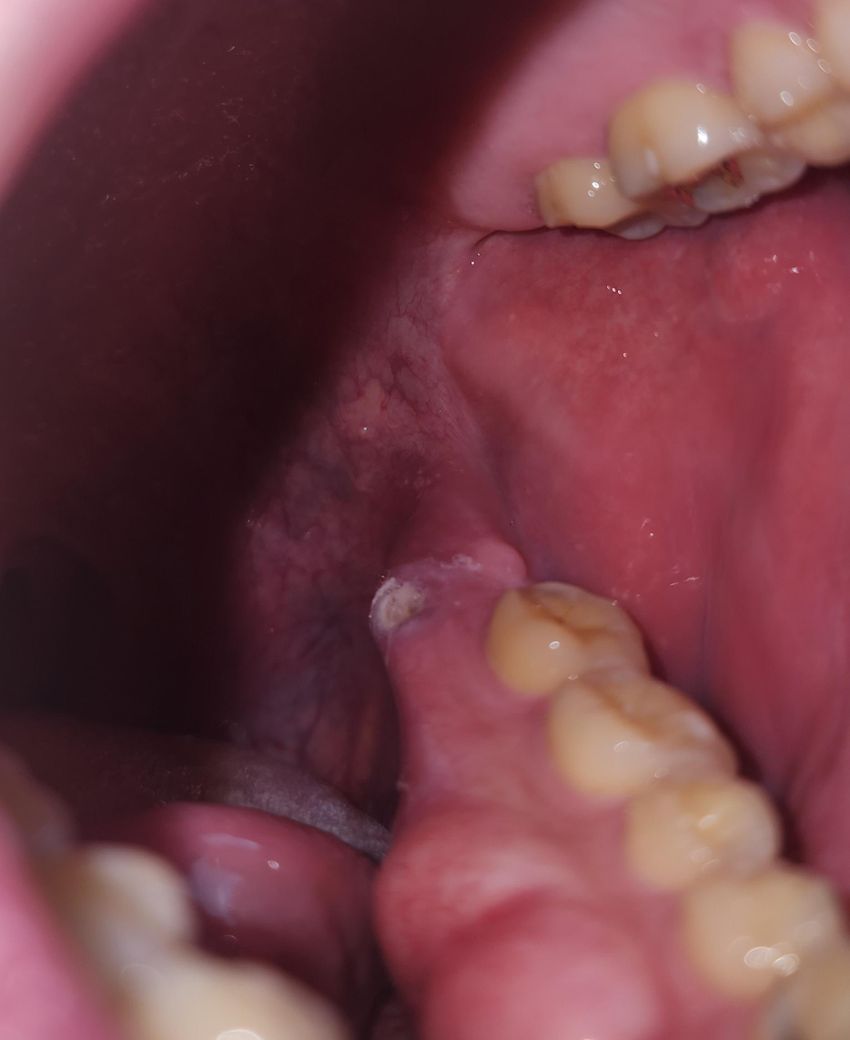

아래턱 어금니 쪽에도 입병이 발병할수있나요?(제 사진 첨부)

아래턱 어금니 쪽에도 입병이 발병할수있나요?

살짝 원형으로 패인 것 처럼 되어있고

흔히 발생하는 입병처럼 통증도 느껴져요

• 1번 째 사진

사진으로만 봤을 경우에는 구내염으로 보입니다.

사진상으로 보면 구내염이 생긴거 같으니 치과에 가셔서 치료를 받으시고 당분간은 자극적인 음식은 피해주시는게 좋을것같습니다.

아래턱 어금니 쪽에도 입병이 발병할수 있으며, 소독용 헥사메딘 가글액과 같은 가글액 사용이 증상 경감에 도움이 됩니다.